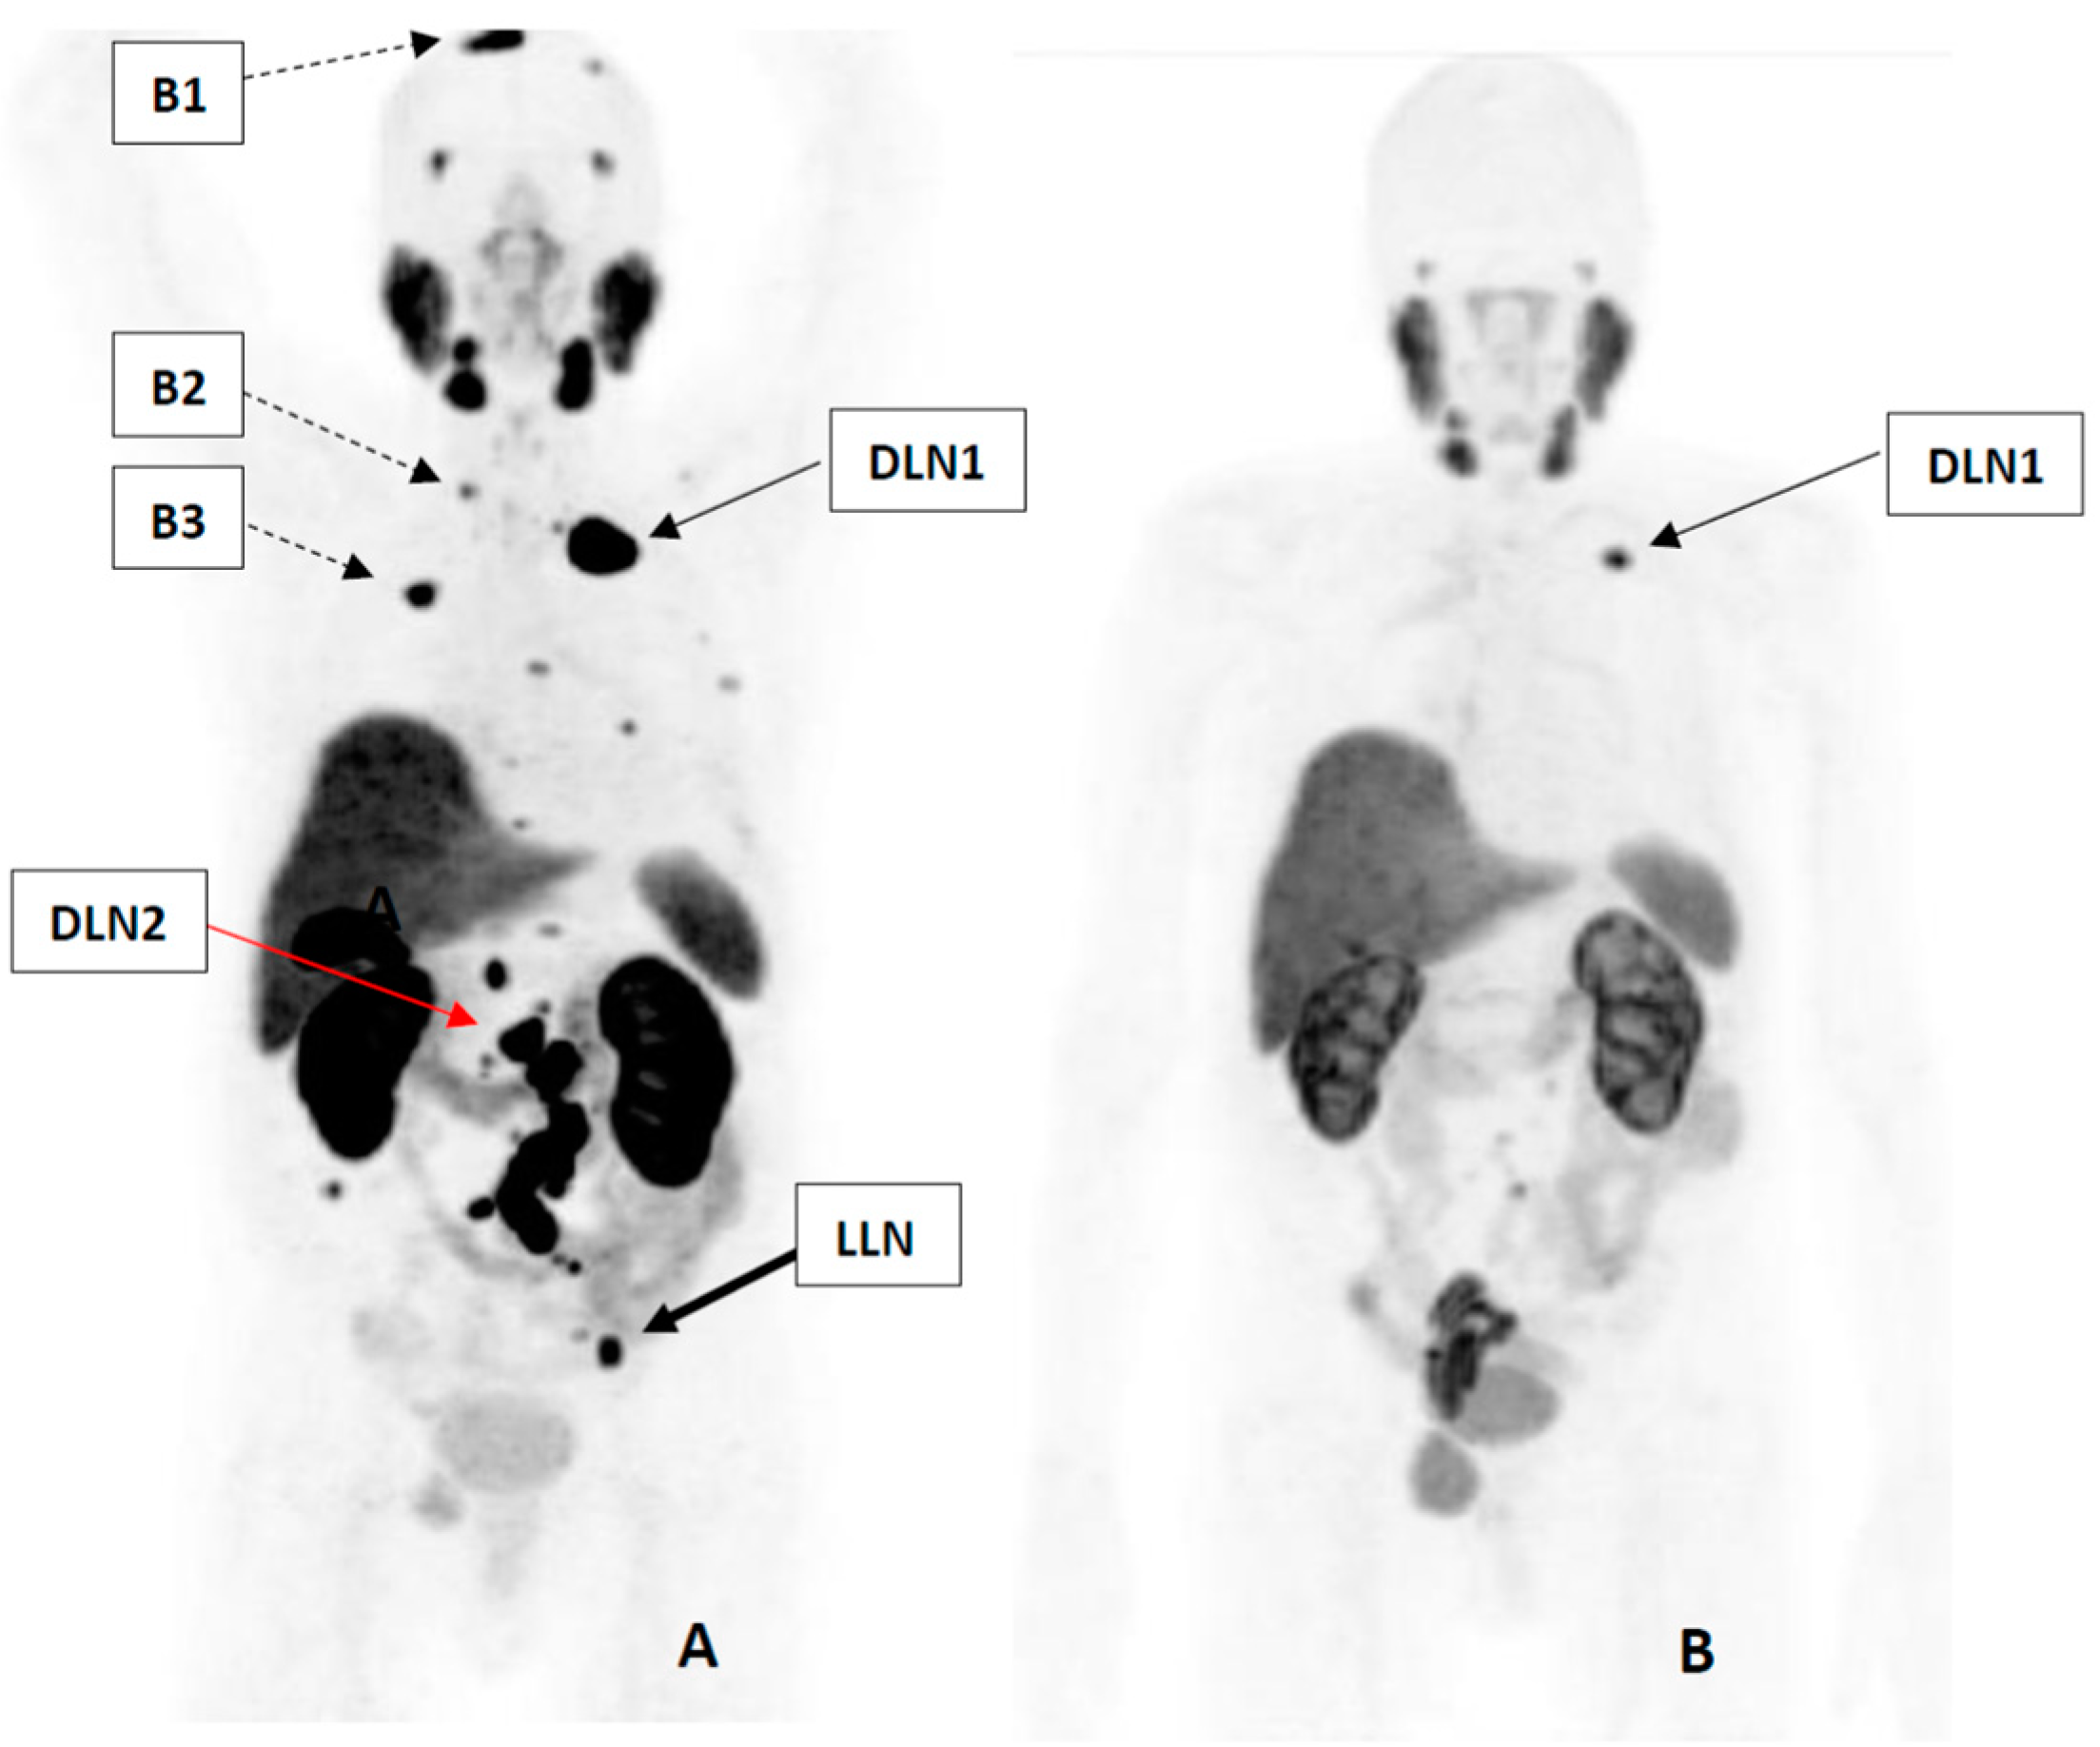

| Cycle of RLT | LLN | DLN1 | DLN2 | B1 | B2 | B3 |

|---|---|---|---|---|---|---|

| Gy/GBq | ||||||

| 1st | 6.89 | 25.57 | 6.8 | 5.55 | 6.25 | 3.75 |

| 2nd | 6.03 | 9.43 | 3.04 | 0.64 | 1.85 | 1.96 |

| 3rd | 2.84 | 8.3 | 2.59 | 0.48 | 0.97 | 1.86 |

| 4th | 2.72 | 7.24 | 2.91 | N/A | N/A | N/A |

| Cycle of RLT | LLN | DLN1 | DLN2 | B1 | B2 | B3 | |

|---|---|---|---|---|---|---|---|

| 1st; Volume (mL) | 0.67 | 3.9 | 0.6 | 1.5 | 0.4 | 0.3 | |

| SUVmax at | 4 h | 2.69 | 33.56 | 24.73 | 9.5 | 5.72 | 2.9 |

| 24 h | 2.64 | 14.36 | 11.2 | 4.21 | 2.33 | 0.96 | |

| 48 h | 2.06 | 9.8 | 8.9 | 2.61 | 1.56 | 0.66 | |

| 2nd; Volume (mL) | 0.37 | 1.22 | 0.4 | 1.5 | 0.4 | 0.3 | |

| SUVmax at | 4 h | 1.14 | 5.73 | 3.56 | 1.83 | 1.23 | 1.32 |

| 24 h | 0.73 | 2.28 | 1.56 | 0.92 | 0.42 | 0.27 | |

| 48 h | 0.68 | 1.43 | 1.28 | 0.64 | 0.29 | 0.15 | |

| 3rd; Volume (mL) | 0.1 | 0.82 | 0.26 | 1.5 | 0.4 | 0.3 | |

| SUVmax at | 4 h | N/A | 3.12 | N/A | 1.02 | N/A | N/A |

| 24 h | N/A | 1.19 | 0.94 | 0.52 | N/A | N/A | |

| 48 h | N/A | 0.76 | N/A | 0.35 | N/A | N/A | |

| 4th; Volume (mL) | 0.1 | 0.5 | 0.13 | 1.5 | 0.4 | 0.3 | |

| SUVmax at | 4 h | N/A | 1.96 | N/A | 0.66 | N/A | N/A |

| 24 h | N/A | 0.79 | 0.5 | 0.32 | N/A | N/A | |

| 48 h | N/A | 0.52 | N/A | 0.22 | N/A | N/A | |